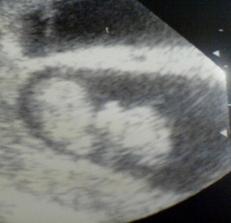

18.září jsme byli na našem 1.IVF... a 8.den od ET se mi "zjevily" nádherné // 🙂... přeju si,aby se všechno vyvíjelo dobře... 29.9 11.den po ET mi pro zhoršení OHSS provedli punkci Douglasova prostoru a odsáli 2 litry žlutého ascitu ☹ Nicméně se mi ulevilo 🙂 HCG ten den 259... 6.10 kontrola HCG - 2950 (18.den od ET)... 10.10 UTZ - čekáme DVOJČÁTKA 🙂 🙂 🙂... 17.10 krvácení a následná hospitalizace, UTZ - dvojčátkům bijí srdíčka, 20.10 HCG - 56000, 25.10 propuštění z nemocnice... 31.10 poslední kontrola v CARu, dvojčátka mají 2 a 2,1 cm... 11.11 UTZ - dvojčátka mají 3 cm... 24.11 UTZ - dvojčátka mají 9 cm (ale moc se mi to měření nezdá, ve čtvrtek na screeningu se ukáže pravda, čeká nás 3D 🙂) 27.11 screening I.trimestru - miminka jsou zdravá, od hlavičky po prdelku mají 7 cm... 19.12 3D - miminko "A" je chlapeček, "béčko" chce zůstat zatím v utajení 🙂 tak snad příště 🙂... 8.1 3D - miminko "B" je holčička 🙂 19.1 echokardiografie - obě srdíčka jsou zdravá 🙂 20.1 screening II.trimestru - vše OK, miminka mají 360 a 364 gramů 🙂 26.1 UTZ - chlapečkovi se ztratil pindík a najednou čekáme 2 holčičky 🙂) Doufám, že už je to definitivní 🙂) 19.2 UTZ 3D4 - holčičky potvrzeny!!! 🙂 mají každá téměř 800 gramů! 🙂 20.3 UTZ - holčičky mají 1700 a 1800 gramů! 8.4 UTZ - holky mají neuvěřitelné váhy 2415 a 2600 gramů! 11.5 nástup do nemocnice... 11.května ve 20,03 se nám akutním císařským řezem narodila Eliška (2970/48) a o minutu později Nelinka (3200/50).Jsme nejšťastnější rodiče na světě! 🙂